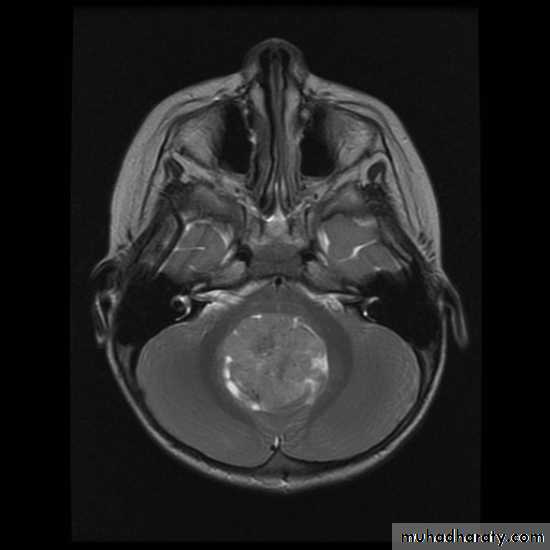

MRIBrain Tumors of Childhood

Histogenesis:* Cell of origin:

glial, neural, primitive, choroid, mixed

* Location:

posterior fossa: 70%

supratentorial: 30%

* Clinical presentation:

location

age

type and grade of the tumor

Brain Tumors of Childhood

Infratentorial70%

esp. < 6 y/o

Supratentorial

30%esp. > 8 y/o